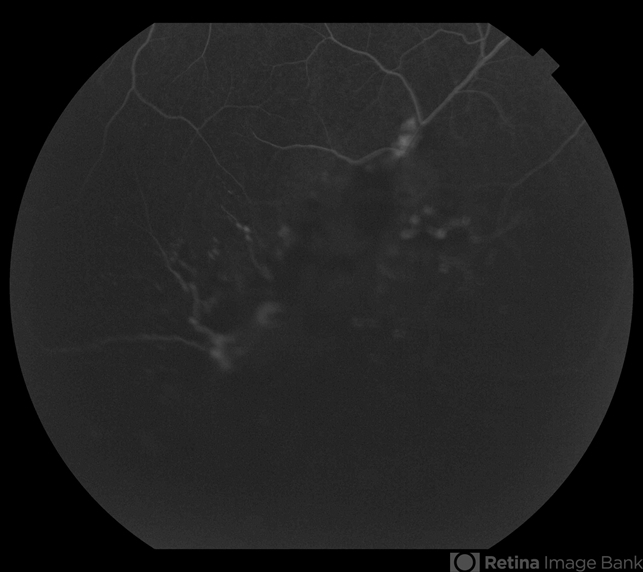

- cavernous hemangioma of the retina

- Robert Ramsay, COA, Southwestern Eye Center Phoenix Arizona

- Fundus camera

- Fundus and fluorescein angiographic images of an 26-year-old male with a peripheral , asymptomatic retinal cavernous hemangioma.